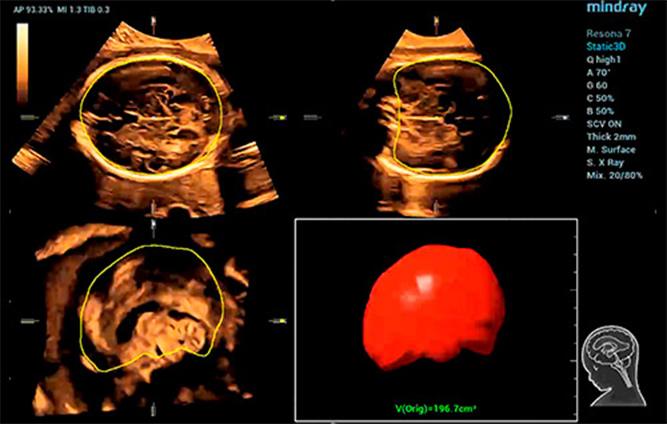

Smart Planes CNS

Ak?ll? ICV: Otomatik intrakraniyal hacim hesaplamas?